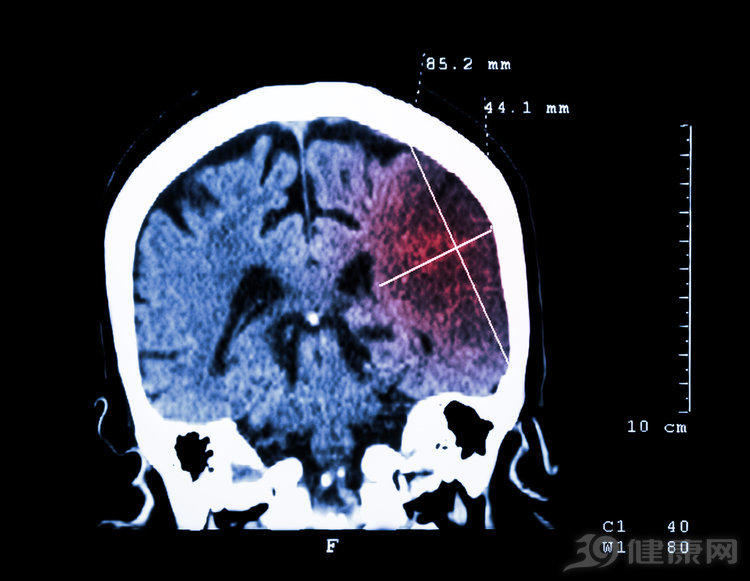

儿子下来后,看到父亲趴在桌面一动不动,慌忙伸手指到父亲鼻孔前,“还有气!”说着赶紧拍打、按摩父亲的肩膀,并摇晃他的身体,反复呼唤他的名字“爸,爸……”,希望能唤醒他。儿子这一操作本出于好心,没想到却加剧了李伯的脑出血。由于病人出血量大,需要紧急手术治疗。

“识别出中风之后,家属不要瞎折腾,应该马上拨打120。”彭兴忠指出,中风分为脑出血和脑梗塞两种,如果不做CT等检查,无法准确判断。自行给病人吃安宫牛黄丸、喂参汤、含参片、喂糖水、按摩摇晃等做法都是错误的。

中风病人如果本来就血压高,喝参汤只会加重病情,血压蹭蹭上升更加厉害。而按摩摇晃病人,确实会让大脑出血更严重。